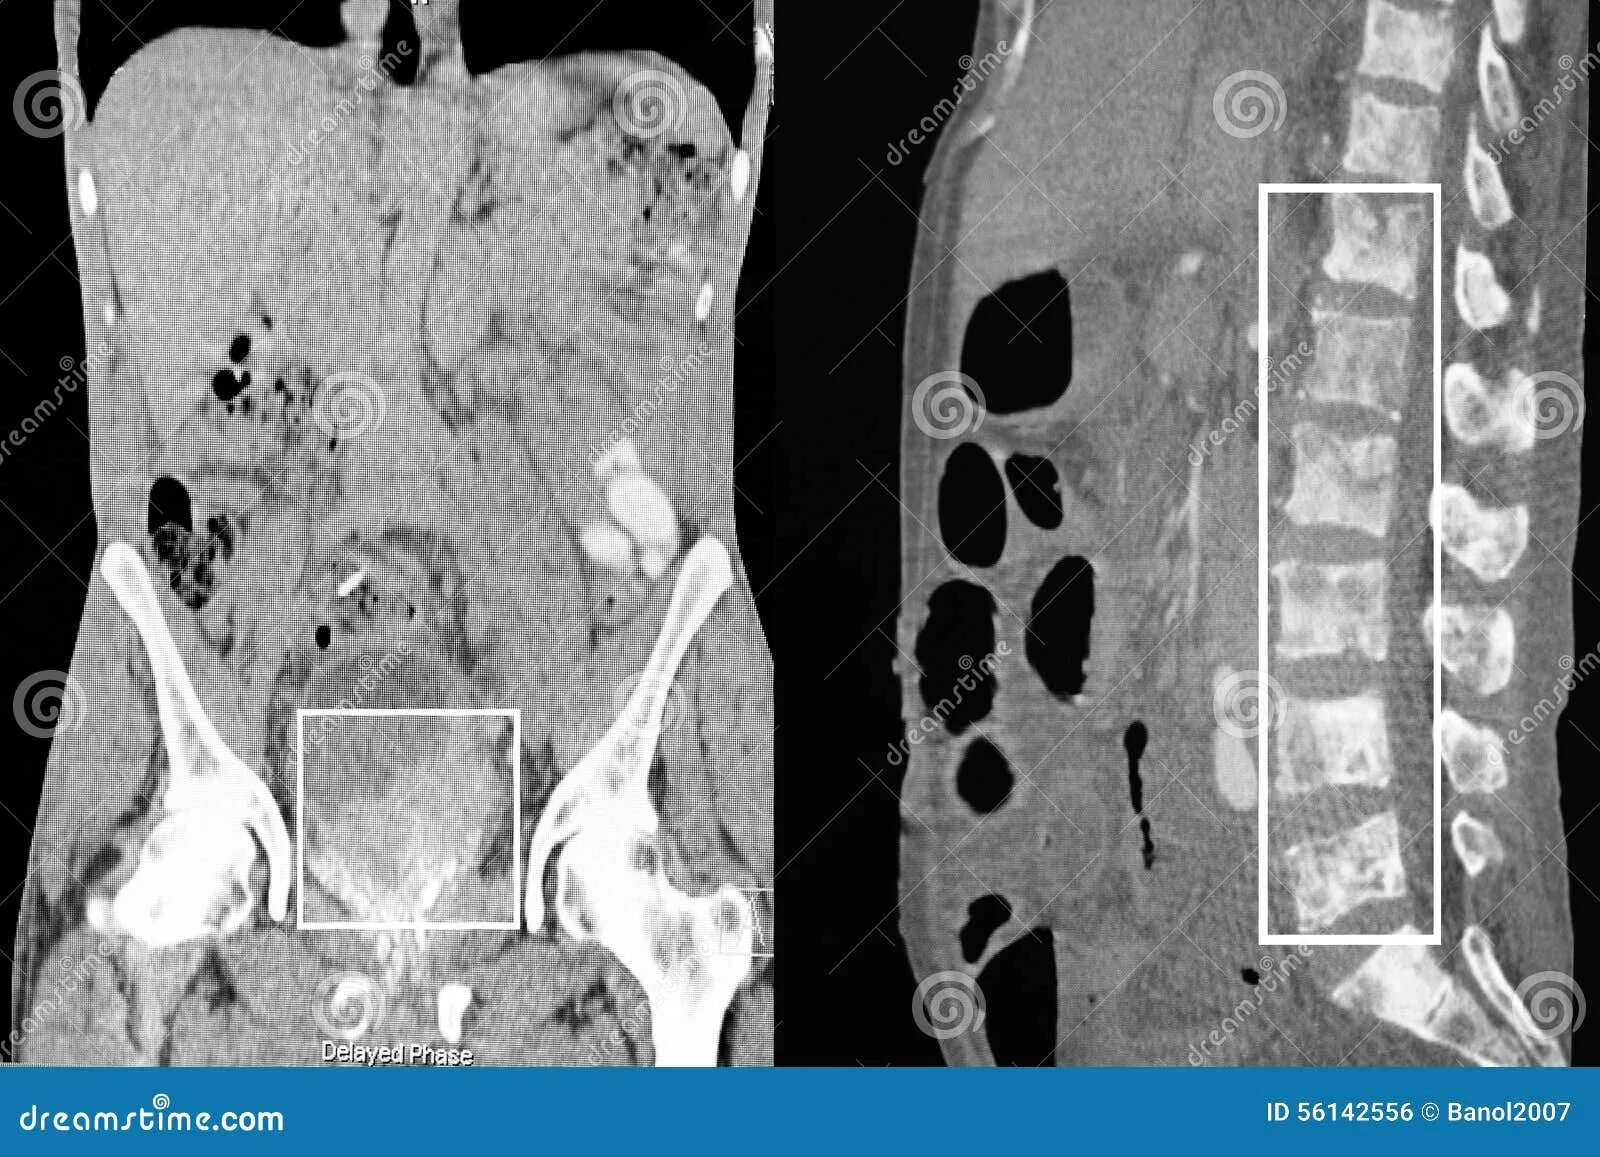

Метастазы в костях какая стадия